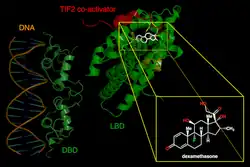

An absolute or relative lack of cortisol causes adrenal crises since there is not enough tissue glucocorticoid activity to preserve homeostasis.[20] Cortisol has a 70 to 120-minute half-life, meaning that cortisol levels fall within several hours of cortisol deprivation.[21] Because cortisol modulates the transcription of genes containing a glucocorticoid response element, this effects many different genes. The physiological effects of low cortisol begin with the loss of the natural inhibitory function of glucocorticoids on inflammatory cytokines. This leads to sharp rises in cytokine concentrations, which can induce fever, lethargy, anorexia, and pain. As a result, low cortisol causes changes in immune-cell levels, including lymphocytosis, eosinophilia, and neutropenia. Low levels of cortisol means that it loses its ability to work with catecholamines to reduce vascular reactivity, which causes vasodilatation and hypotension. Low cortisol has an adverse effect on the liver's metabolism, resulting in hypoglycemia, decreased gluconeogenesis, lower levels of free fatty acids and amino acids in circulation.[20]

Loss of cortisol suppresses nuclear factor κB (NF-κB) and activator protein 1 (AP-1), which allows genes that generate inflammatory proteins to be activated without restriction. This is because cortisol normally inhibits NF-κB's binding to the glucocorticoid receptor. Additionally, through potassium retention and sodium and water loss, mineralocorticoid deficiency is likely to aggravate adrenal crises.[20]